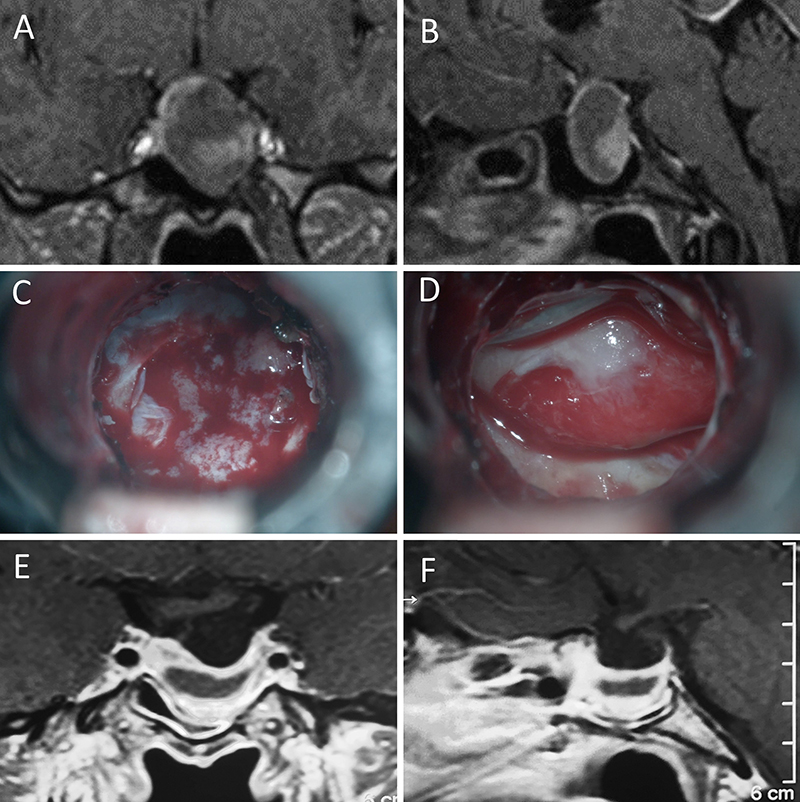

Presentamos 15 casos ilustrativos que consideramos representativos de nuestra serie: 4 enfermos con macroadenomas no funcionantes (figs. 1 a 4); 2 pacientes con macroadenomas con apoplejía (figs. 5 y 6); 4 enfermos con acromegalia (figs. 7 a 10); 3 pacientes con enfermedad de Cushing (figs. 11 a 13) y 2 enfermos con prolactinomas (figs. 14 y 15). El detalle de la presentación clínica de cada paciente y su correspondiente evolución postoperatoria se detalla en el epígrafe de cada ilustración.

Figura 1: Macroadenoma no funcionante en mujer de 65 año

s. Se decidió la cirugía tras evidenciarse crecimiento en los controles. Evolucionó favorablemente desde el punto de vista clínico-radiológico. A-B: RM preoperatoria; C-D: intraoperatorio; E-F: RM postoperatoria.